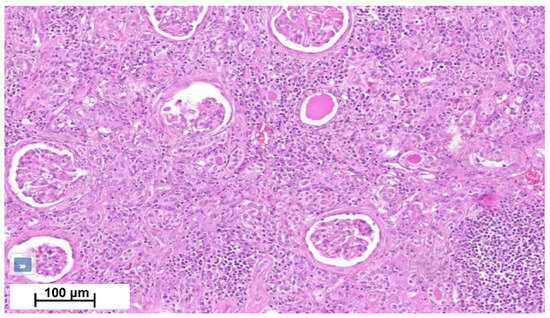

| Kidney involvement | Rarely described. Tubulointerstitial nephritis (rarely granulomatous), nephrocalcinosis and lithiasis | 2 to 10%: mainly nephrocalcinosis, renal stones. Granulomatous TIN in 20% (rarely alone) |